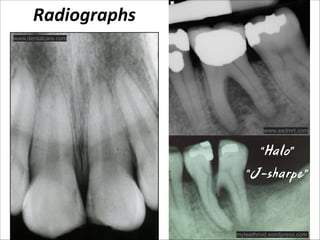

Radiographs

www.dentalcare.com

www.aadmrt.com

“Halo”

“J-sharpe”

myteethnvd.wordpress.com